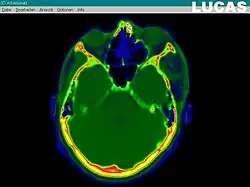

The most important component for CAS is the development of an accurate model of the patient. This can be conducted through a number of medical imaging technologies including CT, MRI, x-rays, ultrasound plus many more. For the generation of this model, the anatomical region to be operated has to be scanned and uploaded into the computer system. It is possible to employ a number of scanning methods, with the datasets combined through data fusion techniques. The final objective is the creation of a 3D dataset that reproduces the exact geometrical situation of the normal and pathological tissues and structures of that region. Of the available scanning methods, the CT is preferred,[1] because MRI data sets are known to have volumetric deformations that may lead to inaccuracies. An example data set can include the collection of data compiled with 180 CT slices, that are 1 mm apart, each having 512 by 512 pixels. The contrasts of the 3D dataset (with its tens of millions of pixels) provide the detail of soft vs hard tissue structures, and thus allow a computer to differentiate, and visually separate for a human, the different tissues and structures. The image data taken from a patient will often include intentional landmark features, in order to be able to later realign the virtual dataset against the actual patient during surgery. See patient registration.

Image analysis involves the manipulation of the patients 3D model to extract relevant information from the data. Using the differing contrast levels of the different tissues within the imagery, as examples, a model can be changed to show just hard structures such as bone, or view the flow of arteries and veins through the brain.